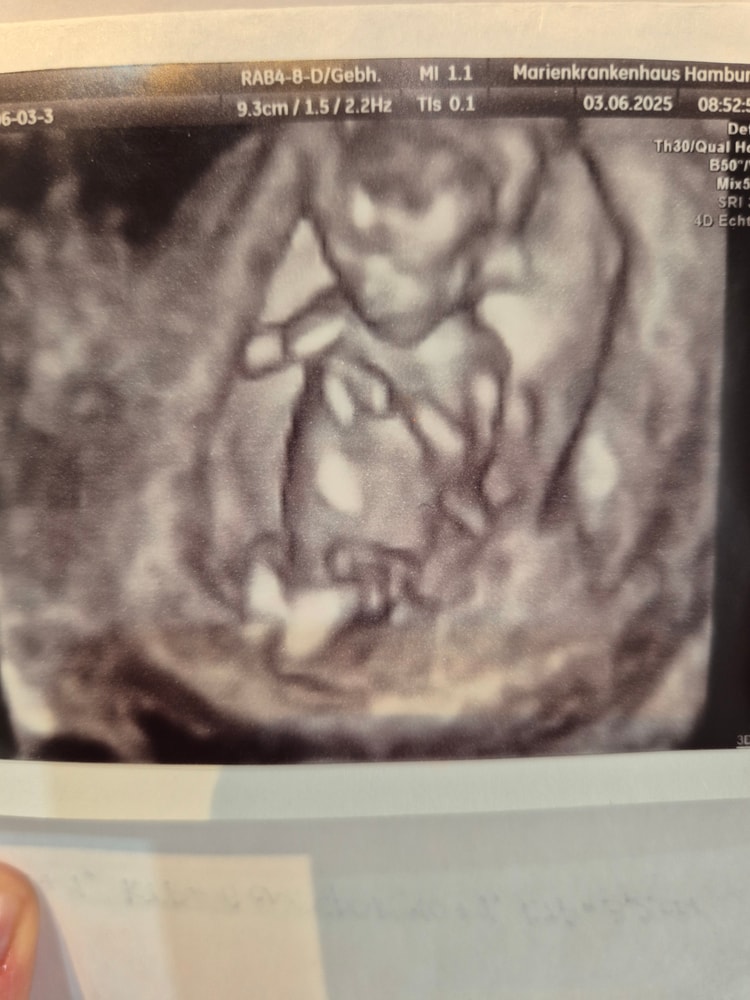

Натали, да , было все затруднительно в этом плане. А сейчас чуть ли не фото лица на 1 скрининге получаешь. Как так то?! Сама не понимаю. 🤔 там бэбик 6 см, а уже все можно разглядеть...

Таня, дада, а вот эти 3D, 4D, где можно даже понять на кого похож. В лучшее время живем)))

Натали, это узишка с 12 недель и уже можно разглядеть, а в 20-25 там уже класс!